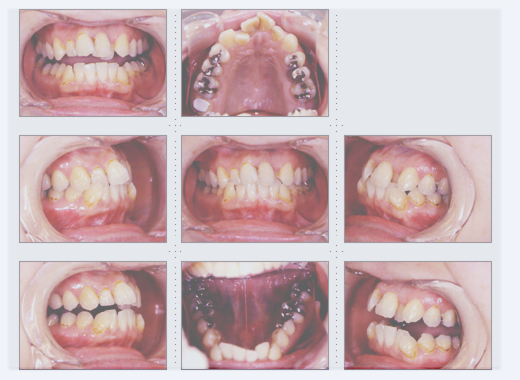

症例3

23才 女性

沖縄のリゾートホテルへ就職が内定している為、通院できるのは4ヶ月という条件で来院。

すべて、3ヶ月で完成し、出発されました。明るい笑顔で接客されていることと思います。